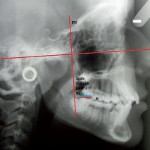

Previsione d’inclusione dei terzi molari e indicazioni alla loro estrazione

Roberto Pertile1

Carlo Mazzanti2

Matteo Brucoli3

Franco Bruno4

Arnaldo Benech5

1 A.S.L. NO – Novara, Ambulatorio di Chirurgia Odontoiatrica, Arona (NO)

2 A.S.L. NO – Novara, Ambulatorio di Chirurgia Odontoiatrica,...